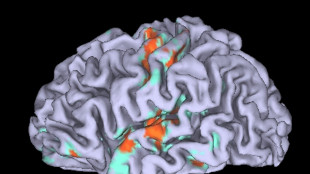

Attività cervello, IA e clima modellati da geometrie nascoste

Studio apre ad algoritmi che imitano l'efficienza della natura

Scoperto un circuito del cervello che libera la creatività

Può essere alterato da lesioni e malattie neurodegenerative